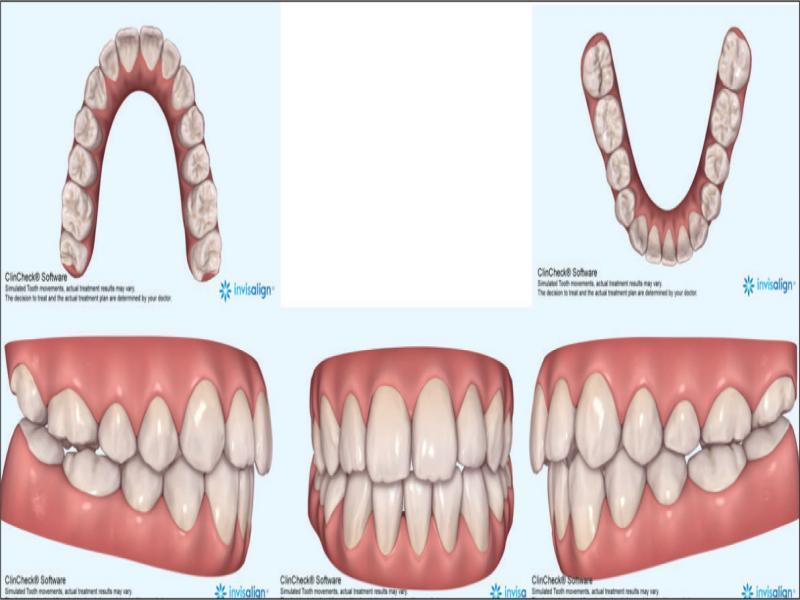

With these considerations, it was planned to treat the patient by the extraction of the lower right central incisor (41), by transverse dental arch expansion, and the management of the vertical relationships by avoiding mechanics that would tend to extrude posterior teeth. The 41 was chosen for extraction as it allowed for alignment of the remaining lower incisors, largely through mesial crown tip. In addition, there was slightly less gingival attachment on 41 and the tooth had a small incisal fracture. The extraction of 31 would perhaps have been more advantageous for the alignment of 32 but would have necessitated a more challenging bodily translation of 41 rather than mainly mesial crown tip. It was considered that clear aligner therapy would be beneficial from a vertical perspective, by minimising the extrusive mechanics inherent to fixed appliances. Figure 4 shows the prescribed finishing position of the dentition. Vertical control was augmented by the placement of occlusal bite pads in the aligners themselves on the occlusal of the molars in both arches to provide a bite-plane effect posteriorly (Figure 5). Furthermore, the absence of fixed appliances serving as a predisposing factor is favourable in managing concerns regarding the patient’s oral hygiene and cariogenic dietary intake.

Invisalign® predicted treatment outcome.